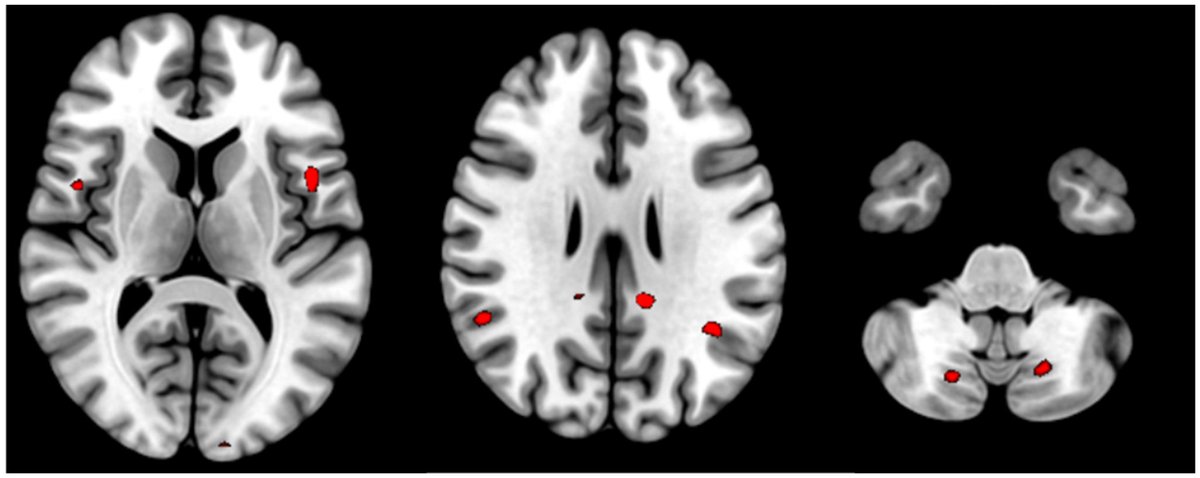

POST-COVID FATIGUE showed INCREASED ACTIVITY in BRAIN REGIONS involved in processing information, perceiving fatigue, and controlling movement

mdpi.com/2075-4418/14/1…Image

2) This study used a brain imaging technique called functional MRI to investigate the neurological basis of persistent fatigue and cognitive issues in people who have recovered from COVID-19. The researchers compared brain activity patterns in 30 patients ... Image

3) ...with post-COVID fatigue syndrome to 20 healthy individuals.

The key findings were that the COVID-19 patients showed significantly higher levels of brain activation in certain regions compared to the healthy controls. Image